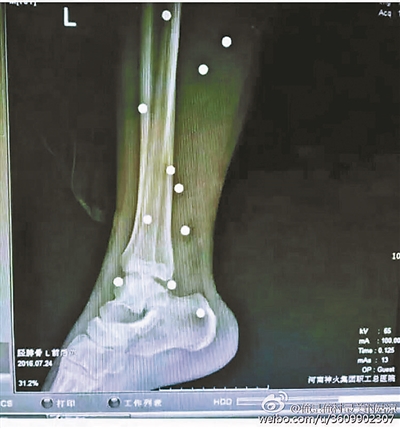

傷者體內(nèi)取出的鋼珠

爆炸導(dǎo)致鋼珠遍布傷者身體各處

黃明的伯伯對北青報(bào)記者表示,由于黃明直接踩到了爆炸物,所以傷情最為嚴(yán)重,“他的腿被炸斷,身體內(nèi)被炸進(jìn)了40多顆鋼珠。手術(shù)后已經(jīng)從體內(nèi)取出29顆鋼珠,還有十多顆鋼珠沒有取出來。”根據(jù)黃明的入院記錄,他全身有多處爆炸傷,且全身多處異物存留。

爆炸發(fā)生時(shí),陳浩的位置與黃明靠得很近,因此也受傷較重。他告訴北青報(bào)記者,經(jīng)過10多個小時(shí)的手術(shù)后,醫(yī)生從他身體里取出了12顆鋼珠。目前,他和黃明兩人經(jīng)過手術(shù)后,已從重癥監(jiān)護(hù)室轉(zhuǎn)至普通病房。其余三人中,陳剛的臀部受傷,當(dāng)天晚上在醫(yī)院清理完傷口后便回了家,而同行的兩名女生身上有一些擦傷。